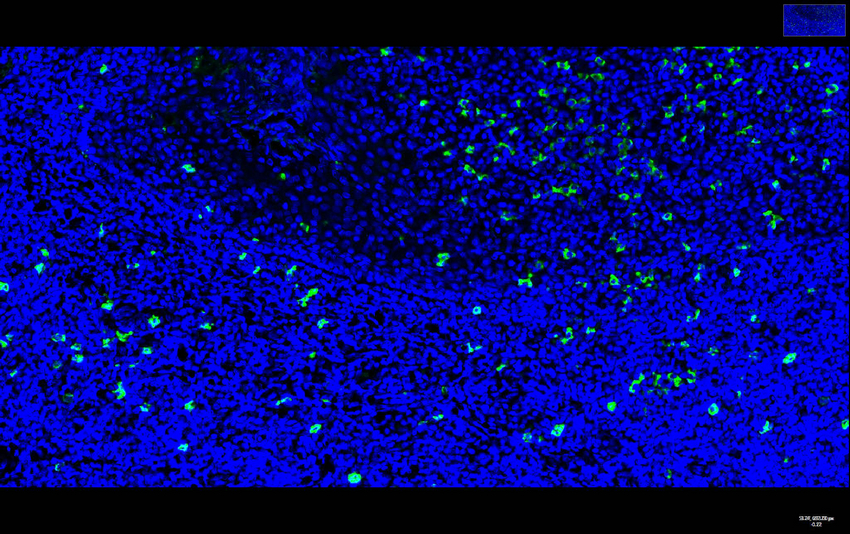

Immunofluorescence analysis of Human tonsils using Bax Polyclonal Antibody.